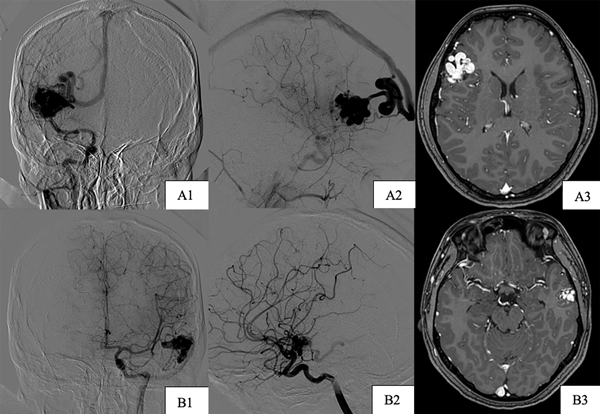

Paciente de sexo femenino, de 17 años, sin antecedentes patológicos, a quien en contexto de estudio por episodio de crisis comiciales de novo se le diagnostican dos MAVs supratentoriales, una frontal derecha de 25 x 29 mm diámetro, con aferencias silvianas, de nido compacto y drenaje hacia el seno longitudinal superior a través de gran vena cortical y otra temporal izquierda de 16 x 11 mm con aferencias silvianas, de nido compacto y drenaje hacia el seno transverso, sin evidencia de signos sugestivos de sangrado (Figura 4). Se decidió estudiar y descartar síndromes congénitos para luego programar la cirugía. Debido a que ninguna de las dos lesiones presentaba factores angiográficos de rotura y por su localización en el hemisferio no dominante se decidió abordar inicialmente la malformación frontal derecha (Figura 5) y 7 meses después se realizó la exéresis de la restante con control angiográfico postquirúrgico satisfactorio y ninguna complicación asociada (Figura 6).

Figura 4. Imágenes preoperatorias caso 2. A) MAV frontal derecha. A1) Incidencia frente. A2) Incidencia perfil. A3) Incidencia axial de RM. B) MAV temporal izquierda. B1) Incidencia frente. B2) Incidencia perfil. B3) Incidencia axial RM.

Figura 6. Imágenes postoperatorias caso 2. Incidencias derechas. A1) Corte coronal. A2) Corte sagital. B) Incidencias izquierdas. B1) Corte coronal. B2) Corte sagital.